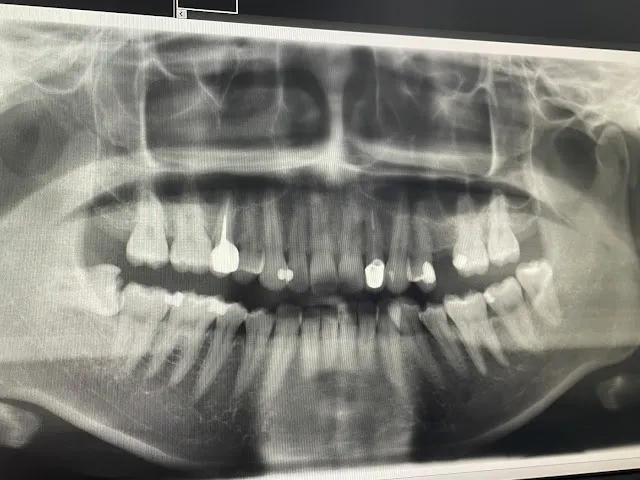

我的牙齒X光照~

今年二月底洗牙時,又被醫生勸說真的該拔掉,蛀很久了,再不處理可能會影響其他顆。我才終於鼓起勇氣面對!只是診所又不敢開這顆牙齒,因為是水平阻生齒,幫我轉診到口腔外科。我上網爬文都說口外是最專業的,萬一有什麼事,大醫院都可以立即處理。當然最後我的體驗也是很好,整個療程都不痛,唯一只有上麻醉時比較痛一點,缺點是掛號回診都只有平日可以選擇,需要請假。